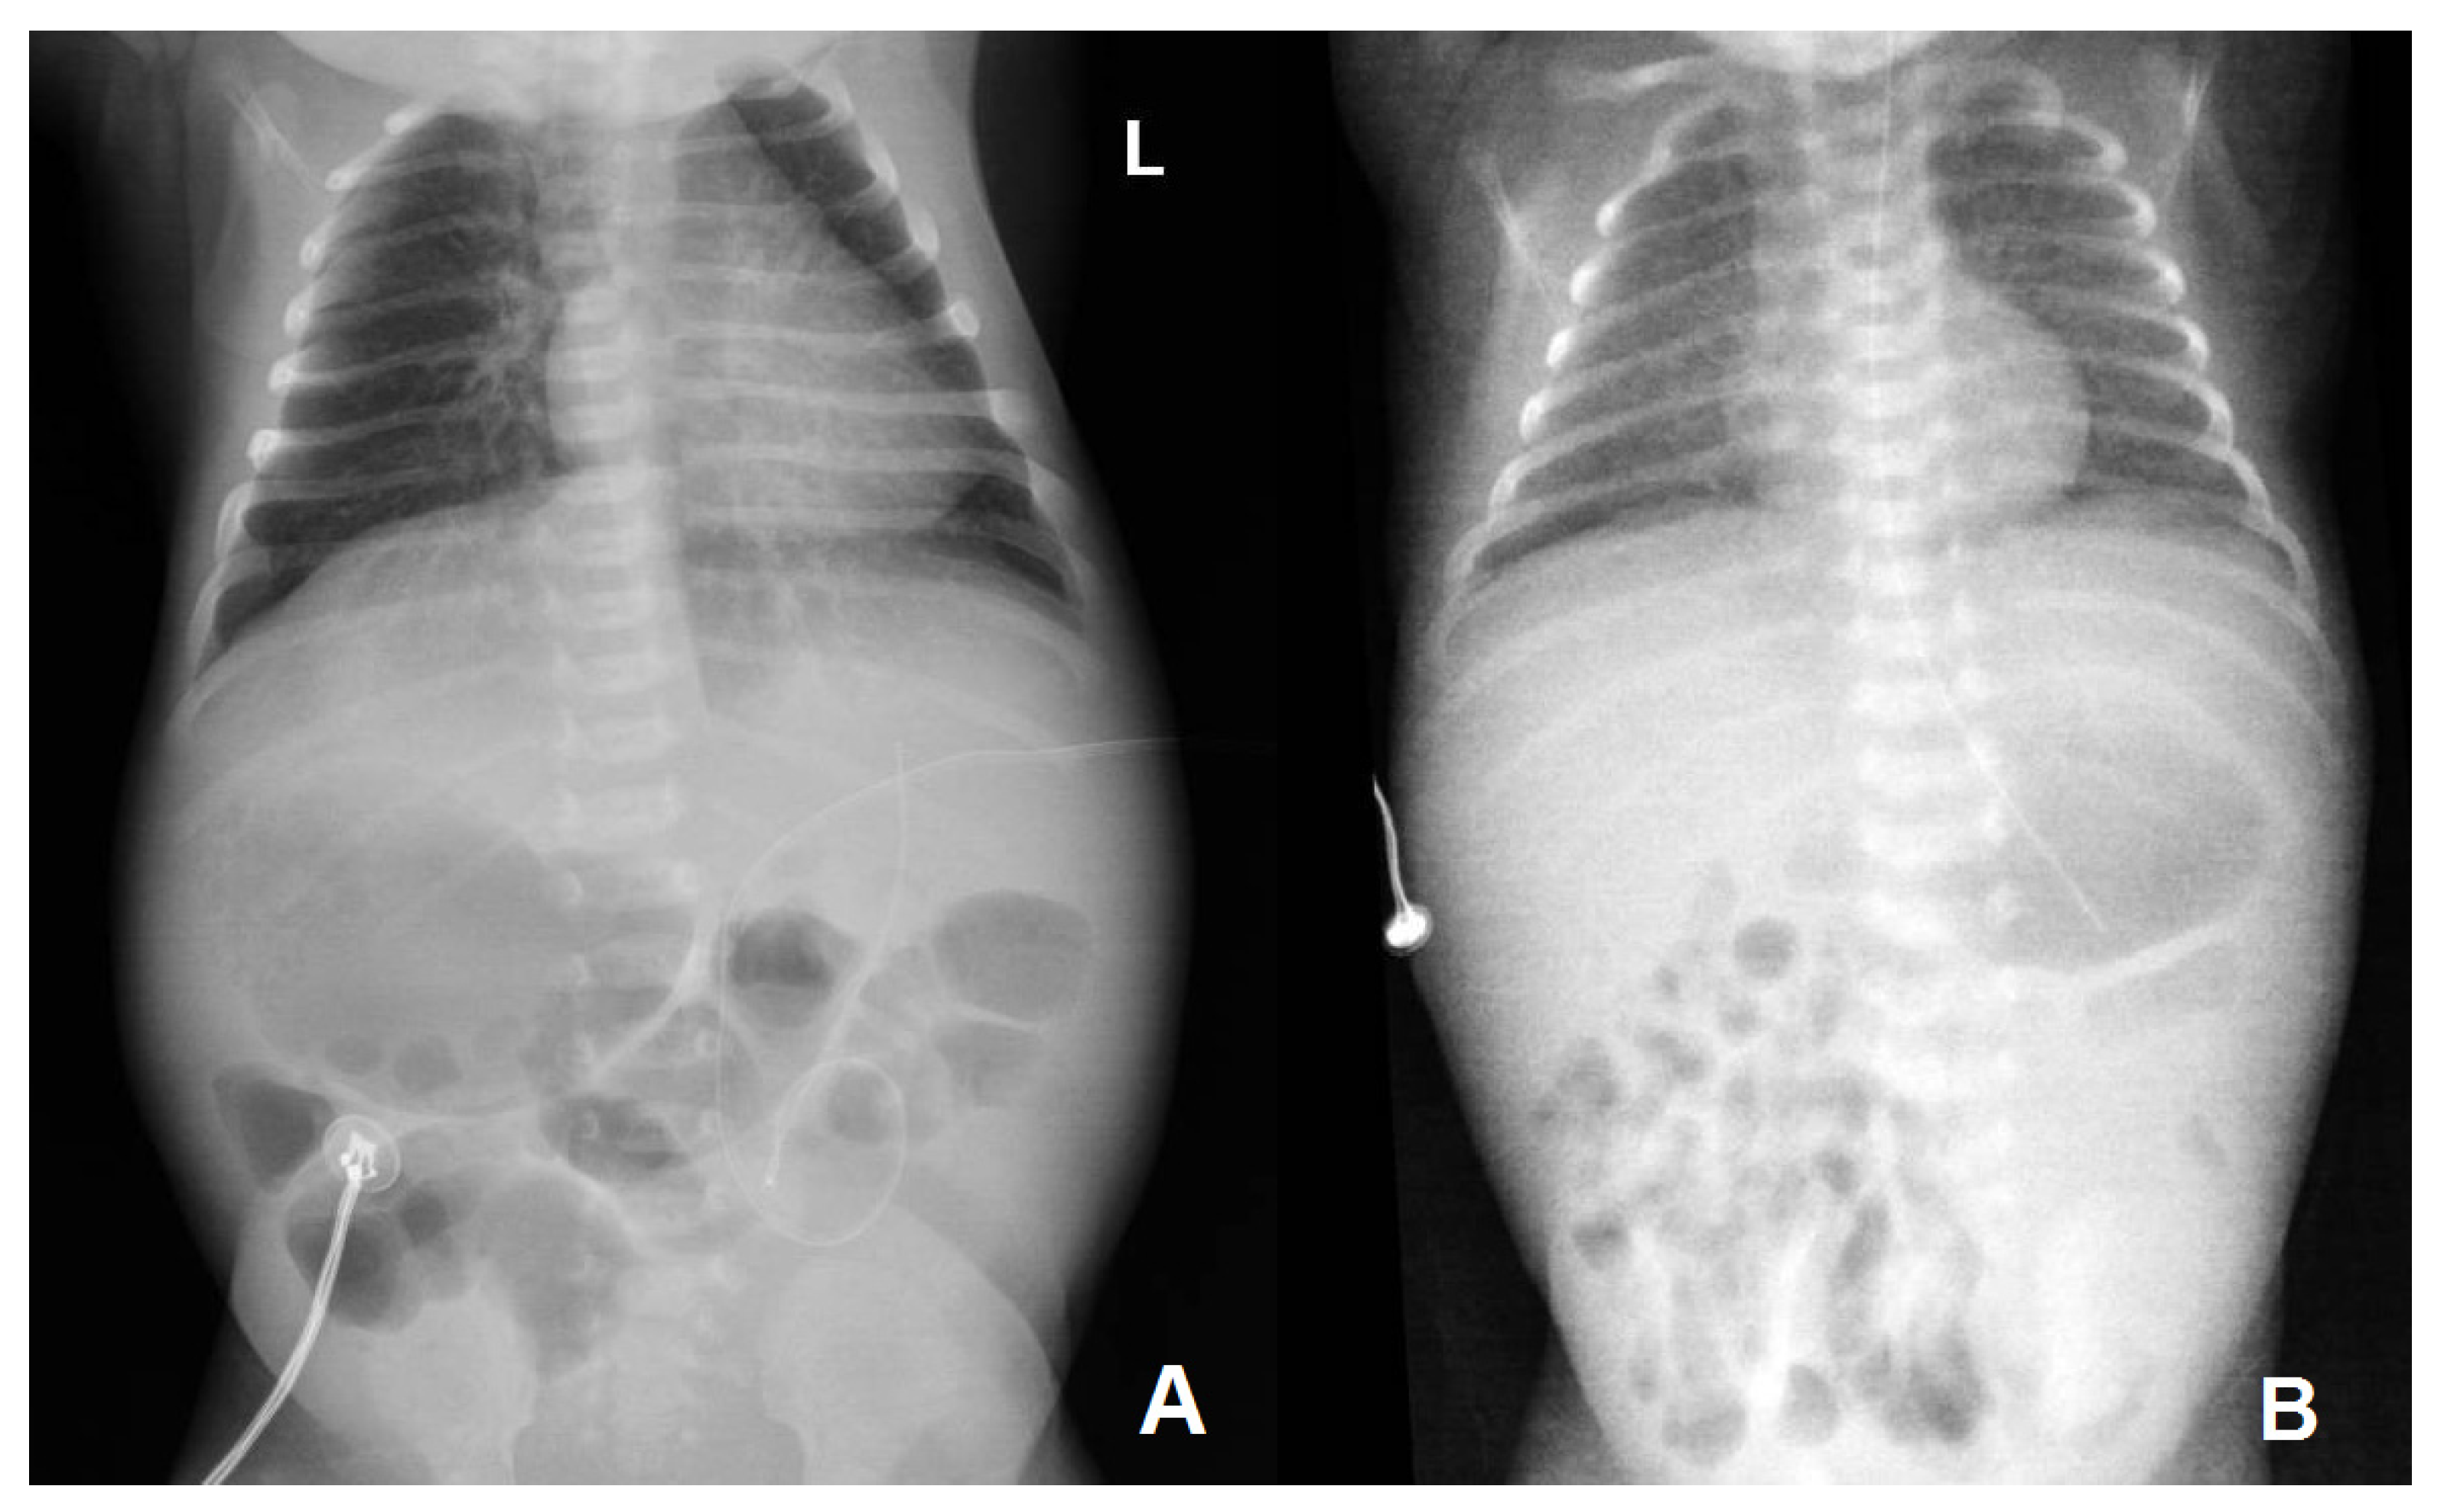

| Thoraco-abdominal radiography | No lung or abdominal involvement | Suggestive of respiratory distress syndrome due to surfactant deficiency on DOL 0; pronounced reticular, micronodular bilateral lung interstitium on DOL 5 | |||||||||||

| Abdominal ultrasound | Abdominal situs inversus on DOL 2; no abdominal parenchymal involvement on DOL 2 and 10 | Gross, inhomogenous, patchy echogenic areas disseminated, almost throughout the entire liver on DOL 9; fine granular echogenic areas limited to the fourth hepatic segment by DOL6 14; normal hepatic ultrasound structure on DOL 45 | |||||||||||